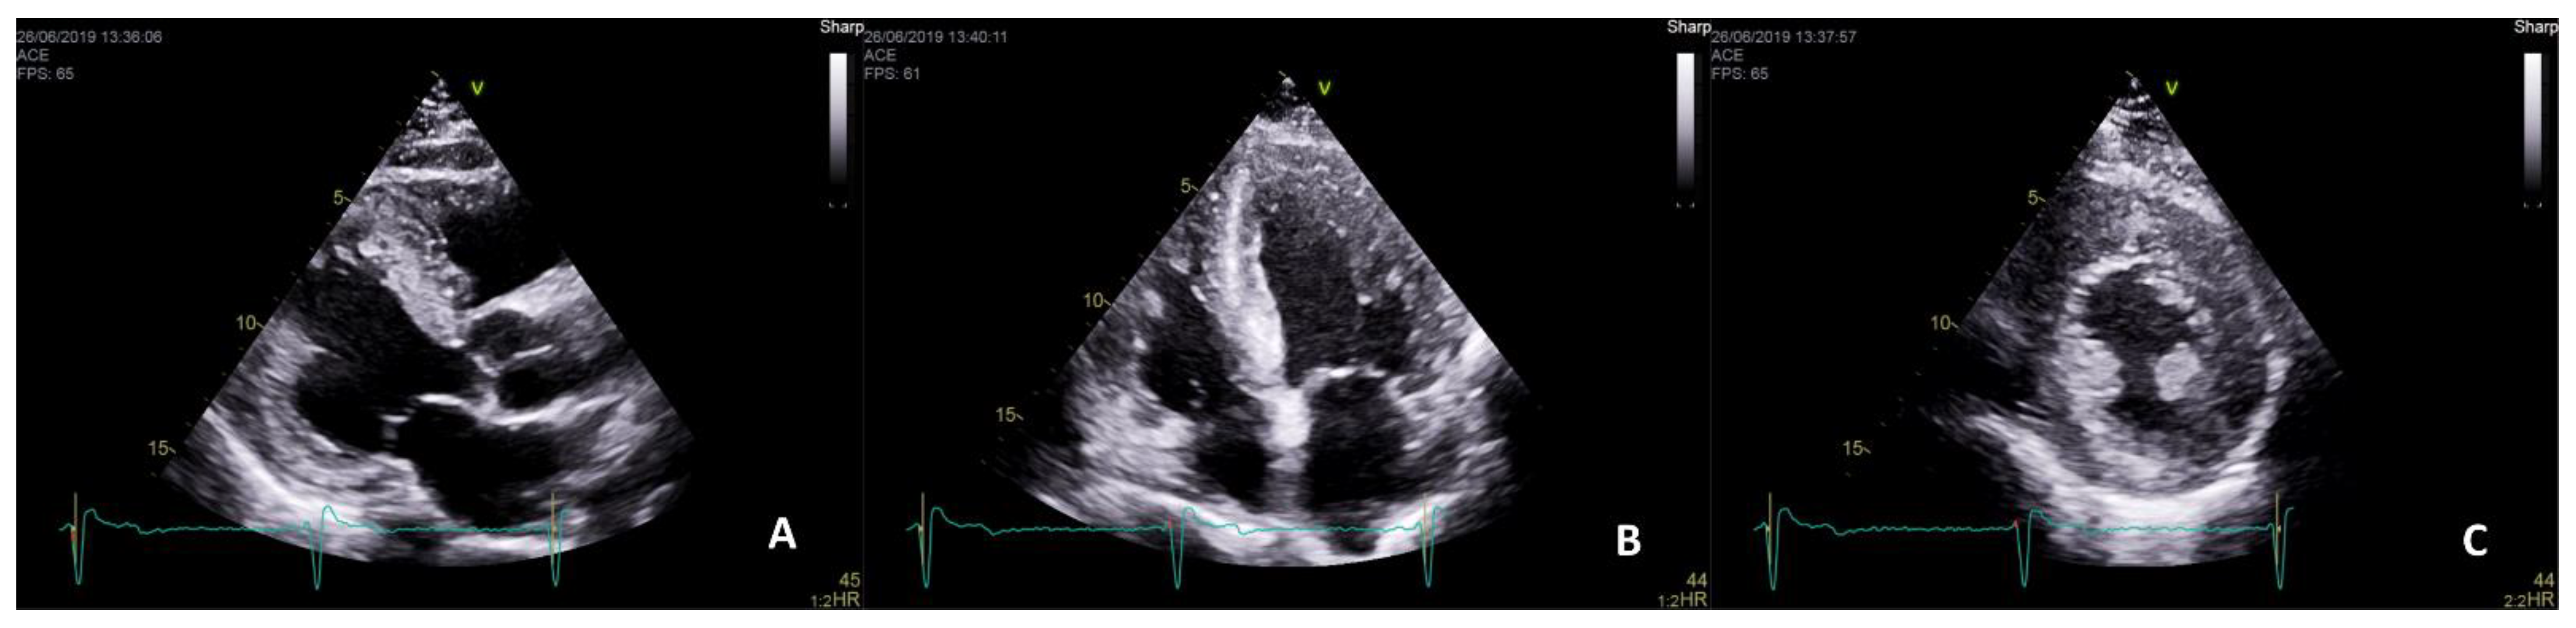

- Pieroni, M.; Chimenti, C.; De Cobelli, F.; Morgante, E.; Del Maschio, A.; Gaudio, C.; Russo, M.A.; Frustaci, A. Fabry’s Disease Cardiomyopathy: Echocardiographic detection of endomyocardial glycosphingolipid compartmentalization. J. Am. Coll. Cardiol. 2006, 47, 1663–1671. [Google Scholar] [CrossRef] [Green Version]

- Mundigler, G.; Gaggl, M.; Heinze, G.; Graf, S.; Zehetgruber, M.; Lajic, N.; Voigtländer, T.; Mannhalter, C.; Sunder-Plassmann, R.; Paschke, E.; et al. The endocardial binary appearance (’binary sign’) is an unreliable marker for echocardiographic detection of Fabry disease in patients with left ventricular hypertrophy. Eur. J. Echocardiogr. 2011, 12. [Google Scholar] [CrossRef] [Green Version]

- Niemann, M.; Liu, D.; Hu, K.; Herrmann, S.; Breunig, F.; Strotmann, J.; Störk, S.; Voelker, W.; Ertl, G.; Wanner, C.; et al. Prominent Papillary Muscles in Fabry Disease: A Diagnostic Marker? Ultrasound Med. Biol. 2011, 37, 37–43. [Google Scholar] [CrossRef]